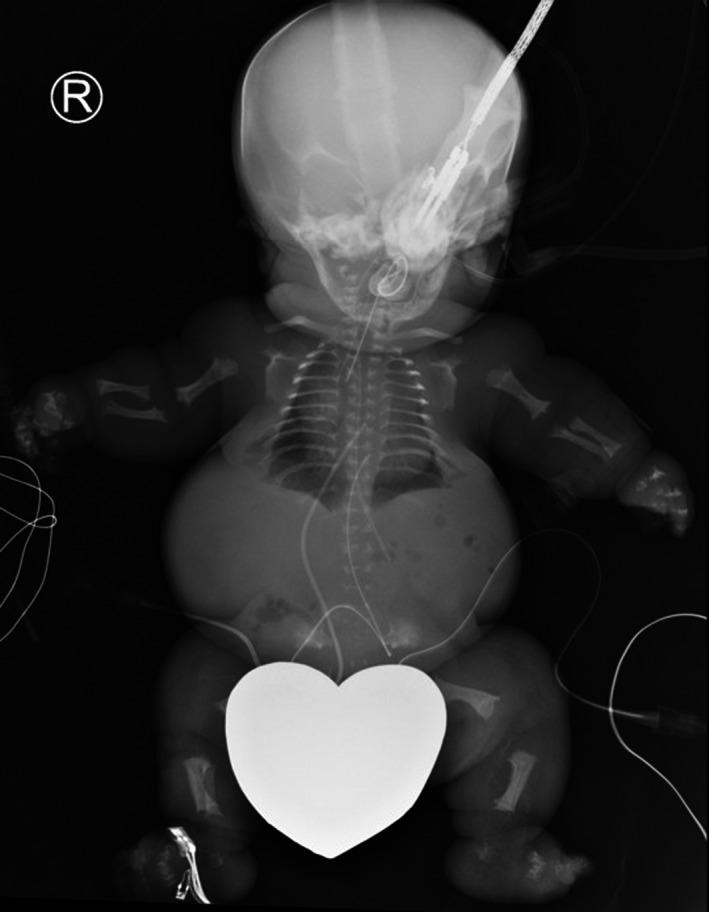

This report describes two patients with INPPL1- related skeletal dysplasia diagnosed prenatally. A literature review is conducted to find out if high-lethality is associated with particular pathogenic variants in INPPL1 gene. Prediction of lethality in the prenatal setting has an impact on perinatal management. Some frameshift variants in INPLL1 gene are uniquely observed in lethal cases; however, more patients are needed to confirm the correlation.

本报告描述了两名产前诊断为与INPPL1相关的骨骼发育不良的患者。进行了文献综述,以确定高致死率是否与INPPL1基因中的特定致病变异相关。产前环境中致死率的预测对围产期管理有影响。INPLL1基因中的一些移码变异仅在致死病例中观察到;然而,需要更多患者来证实这种相关性。